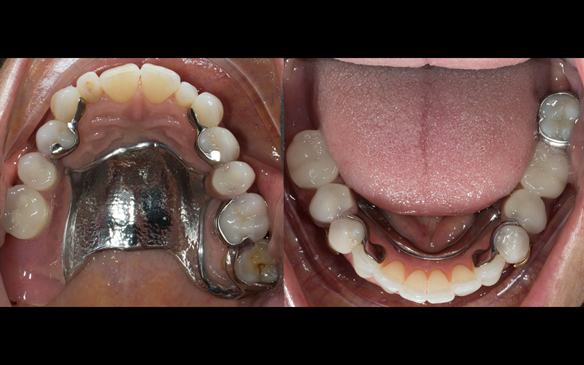

This newsletter describes in step by step detail Angela's transition through immediate partial dentures to crown supported definitive metal based dentures.

This 58 year old woman was referred to me by her general dental practitoner for treatment.

The clinical situation and treatment process is shown in detail below with photographs. I (Finlay Sutton) provided the clinical work and Rowan Garstang provided the technical work.